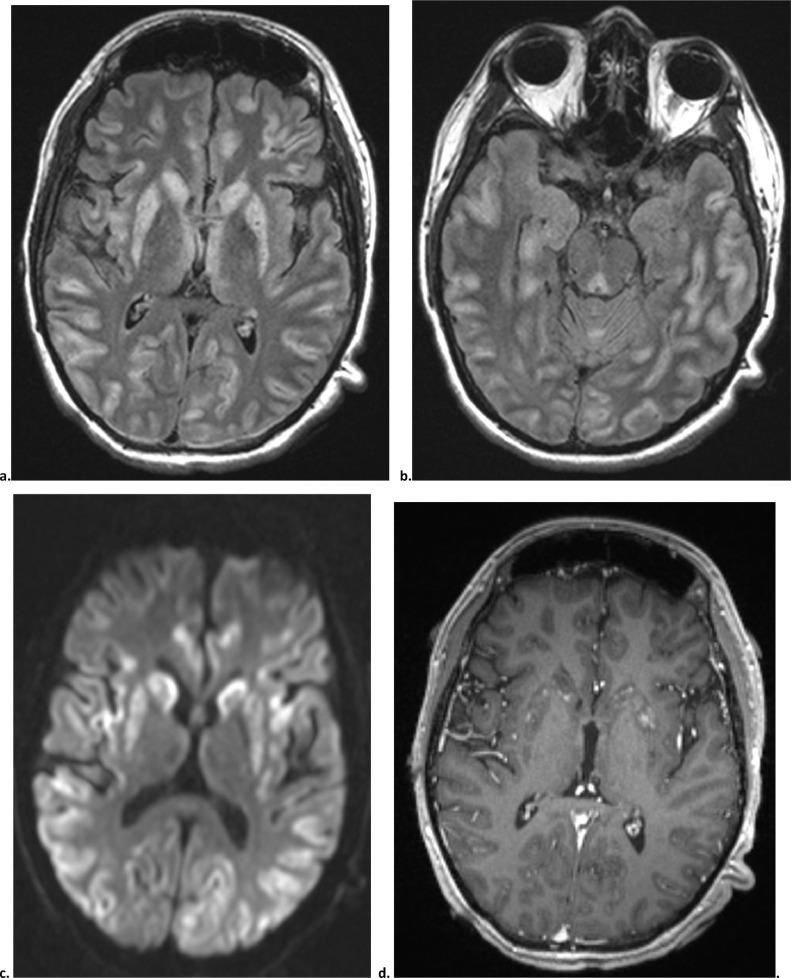

Biotin-Thiamine-Responsive Basal Ganglia Disease is an extremely rare autosomal recessive neurometabolic disorder characterized by recurrent waxing and waning episodes of subacute encephalopathy and seizures. High dose biotin and thiamine administration has been shown to improve symptoms within days, and the symptoms may reappear rapidly if supplementation is discontinued. Here we present a case of a 20-year-old male with classical clinical and imaging findings of Biotin-Thiamine-Responsive Basal Ganglia Disease, with a 12-year delay in diagnosis, finally diagnosed after presenting at our institution based on imaging and subsequent reexamination of exome sequencing. In this report, we review the classic imaging findings in this disease and examine why making the diagnosis can be extremely challenging due to its wide differential. Both clinically and radiographically, this condition demonstrates significant overlap with a vast array of disease entities, ranging from viral or autoimmune encephalitis to metabolic disorders. Finally, we discuss the various negative prognostic predictors described in the literature, several of which were observed in this patient's clinical course.

生物素-硫胺素反应性基底节疾病是一种极其罕见的常染色体隐性神经代谢障碍疾病,其特征为亚急性脑病和癫痫发作反复发作,症状呈进行性加重和缓解。已证实,高剂量生物素和硫胺素治疗可在数天内改善症状,若停止补充,症状可能迅速复发。本文报告一例20岁男性患者,具有生物素-硫胺素反应性基底节疾病的典型临床和影像学表现,诊断延迟12年,最终在我院就诊时,根据影像学检查及随后对外显子组测序结果的复查得以确诊。在本报告中,我们回顾了该疾病的经典影像学表现,并探讨了由于其鉴别诊断范围广泛,为何做出诊断极具挑战性。在临床和影像学方面,该疾病与从病毒性或自身免疫性脑炎到代谢紊乱等众多疾病实体存在显著重叠。最后,我们讨论了文献中描述的各种不良预后预测因素,其中一些在该患者的临床病程中有所观察。